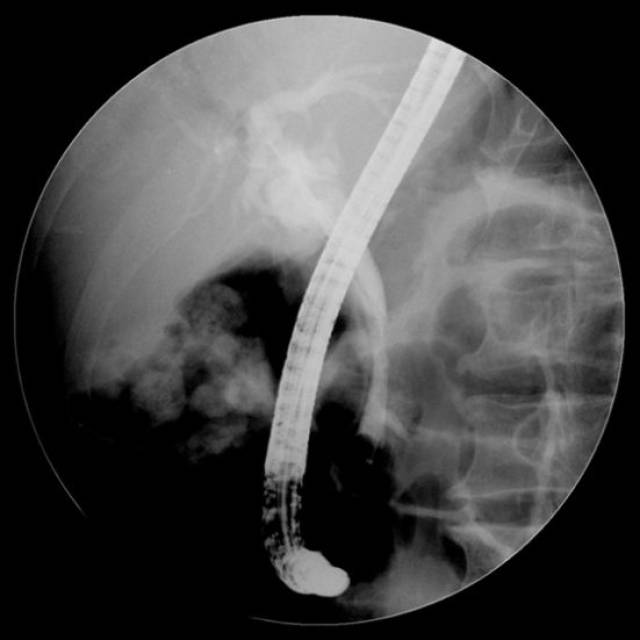

ercp造影导管图片

原来有一种造影叫ercp - 美篇

图片尺寸1750x1533